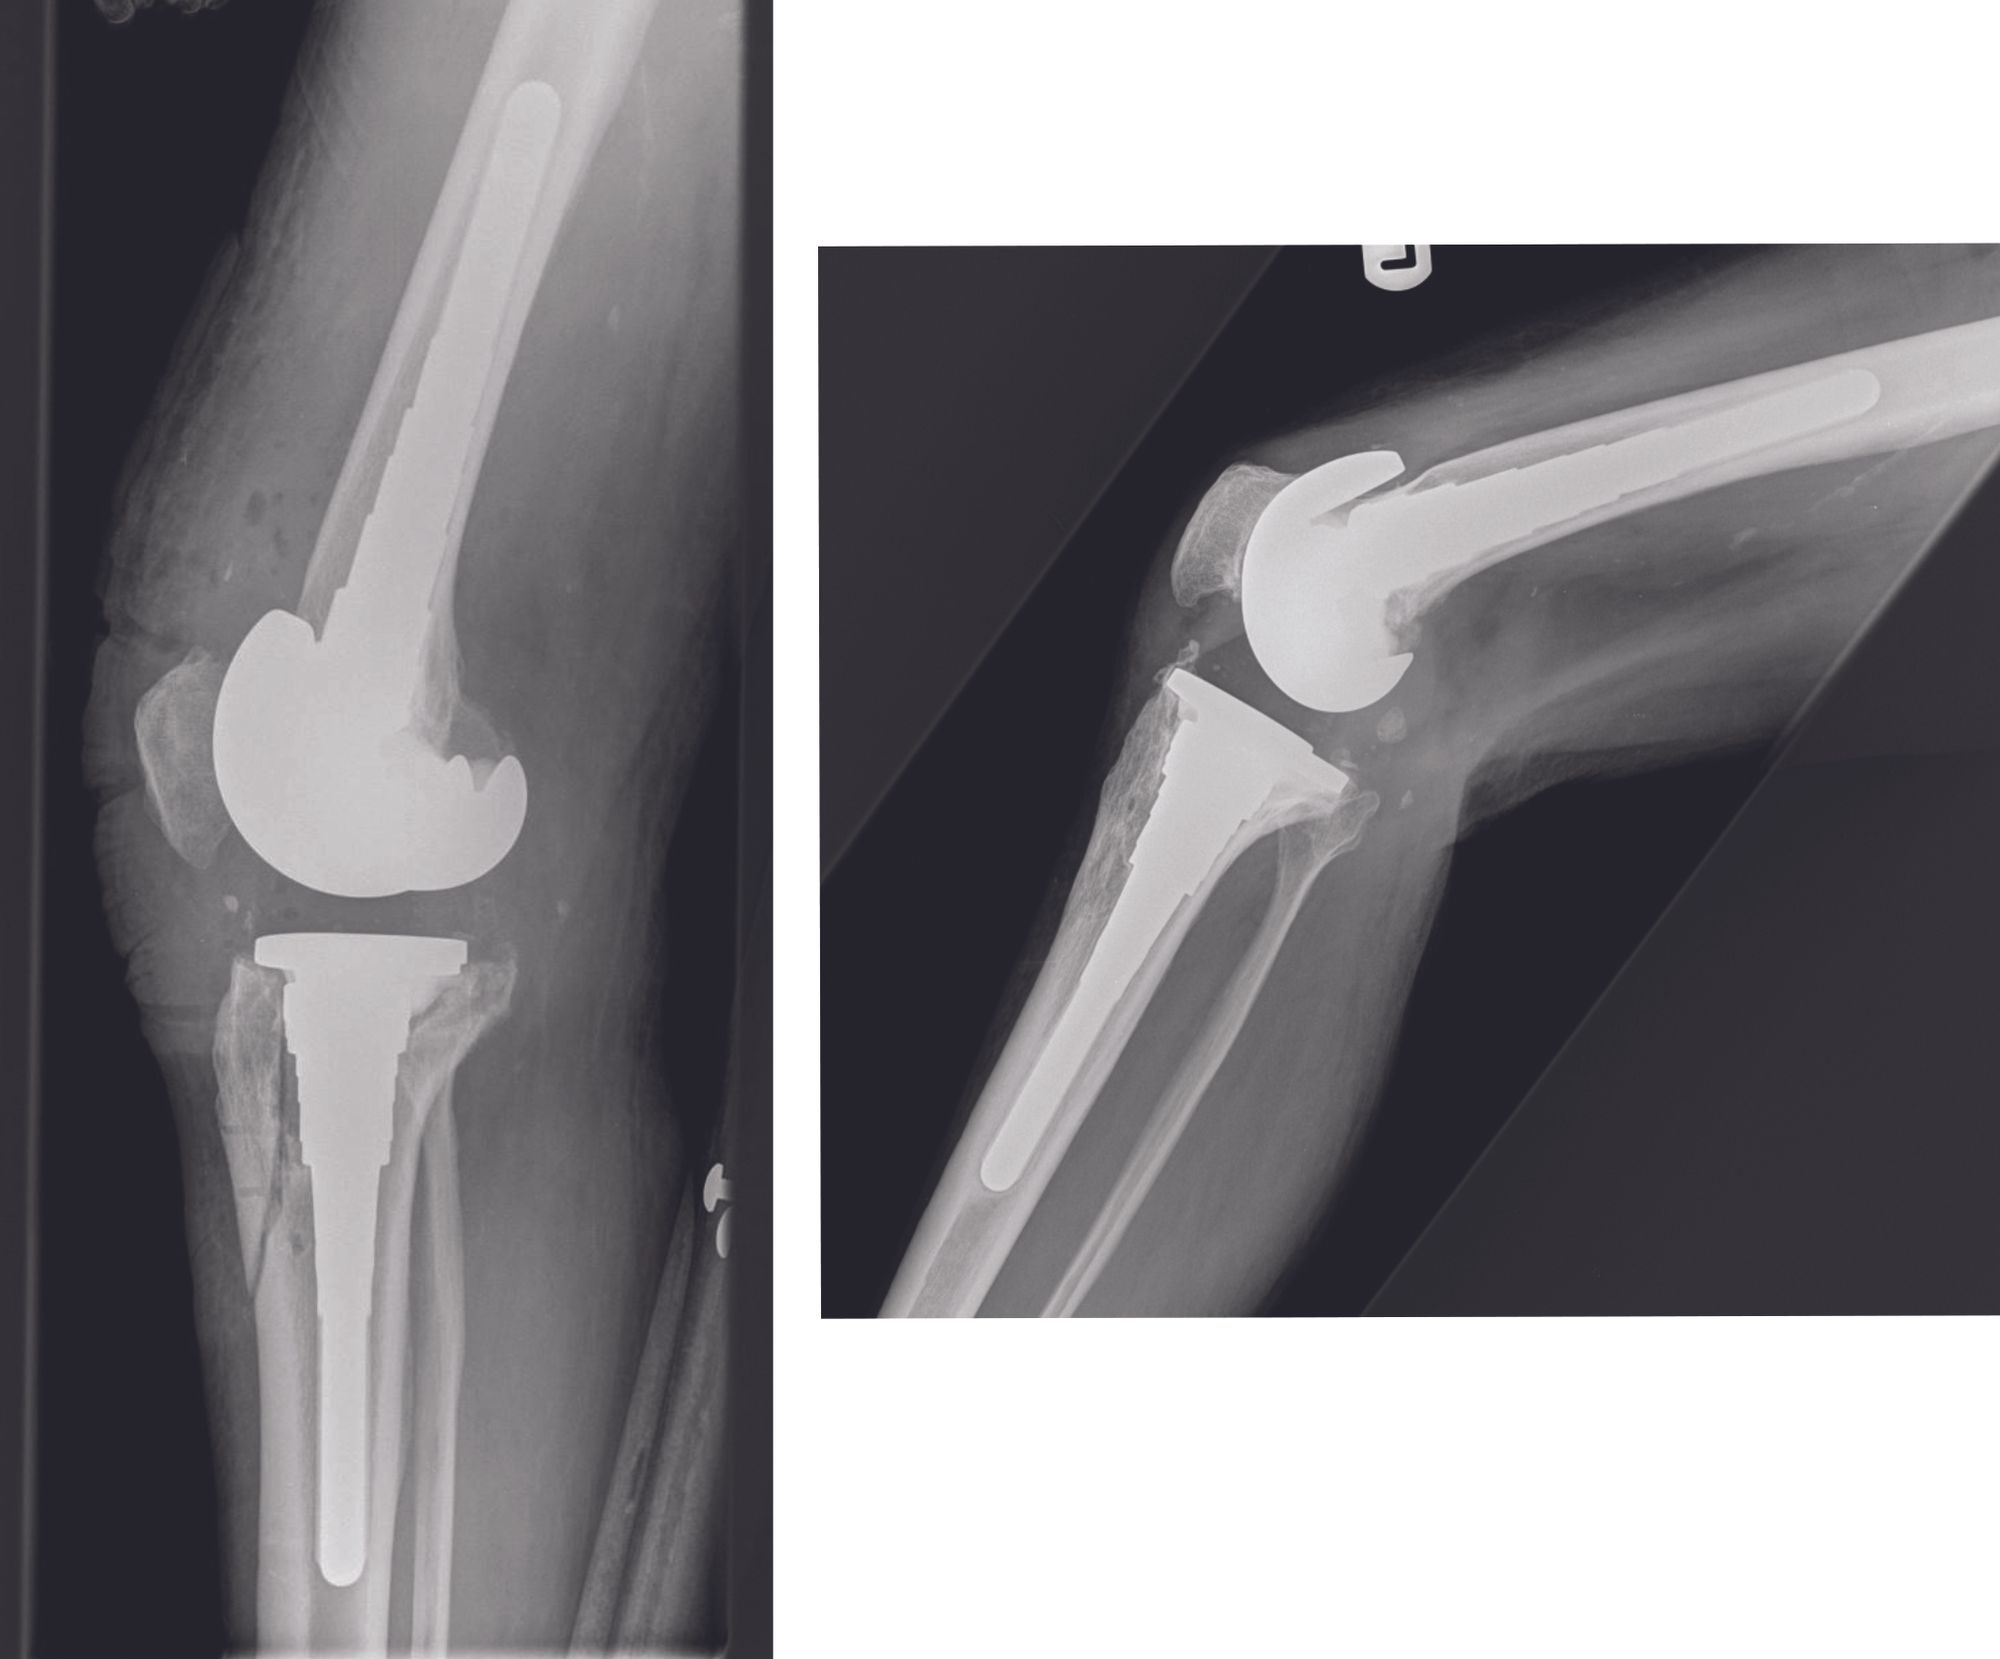

Post-operatively patients are allowed full range of motion and weight bearing with no brace needed. The post-operative radiographs (figure 5) are as per protocol (we advise educating radiologists on the use of the TCO to avoid misreporting). Follow-up regimen does not differ from other revision knee arthroplasty patients.

We first proposed ligature fixation technique of TCO in 2008. Subsequently, in our series of 181 TCOs we showed that there was 100% union at mean period of 11 weeks with no extensor mechanism failure or complications related to the suture material at average follow up of 22 months [6]. This has demonstrated the utility of this technique gaining satisfactory outcomes whilst avoiding hardware problems.